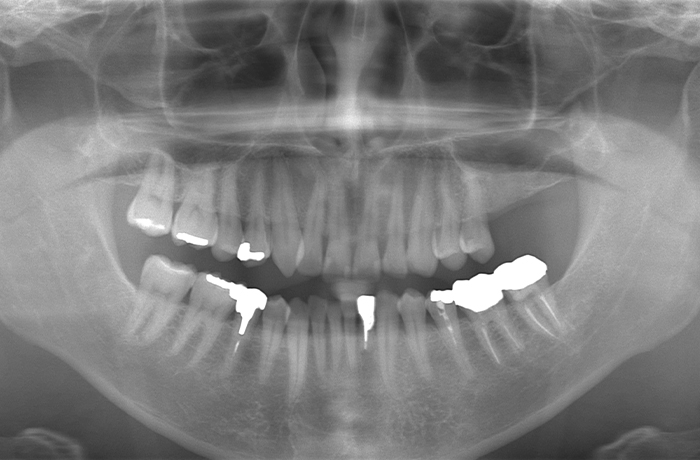

治療前

口腔内写真とレントゲン写真

左上6・7番欠損部は骨吸収が進行し、上顎洞底までの残存骨高径は5mm未満でした。

咬合支持が失われ、対合歯の挺出傾向がありました。